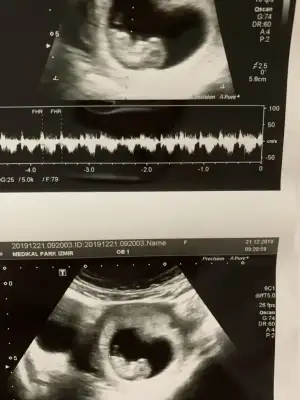

11+6 yorumlarsan sevinirim 😂bu arada doktor birşey söyledi ama net değil.

Benim de 11+6 😍🧿 bana da yorum yapar mısın? Ikra meyra Ikra meyra

• AD0ED4F4-7689-4163-ADA1-AD000ACA47A2.webp

AD0ED4F4-7689-4163-ADA1-AD000ACA47A2.webp

32,6 KB · Görüntüleme: 50